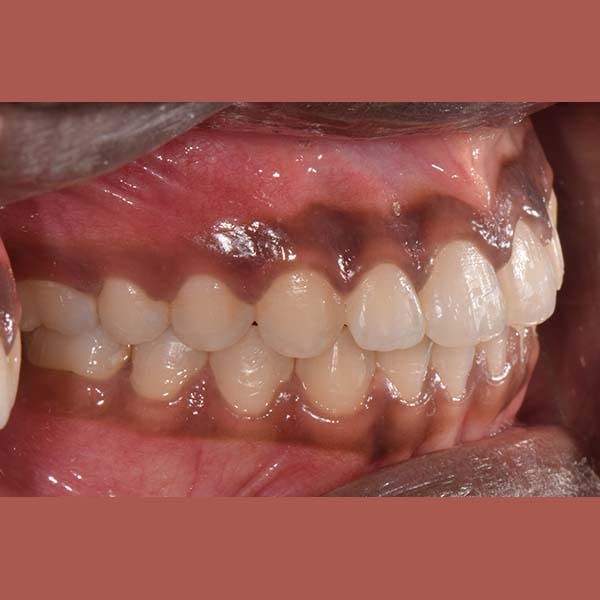

BEFORE